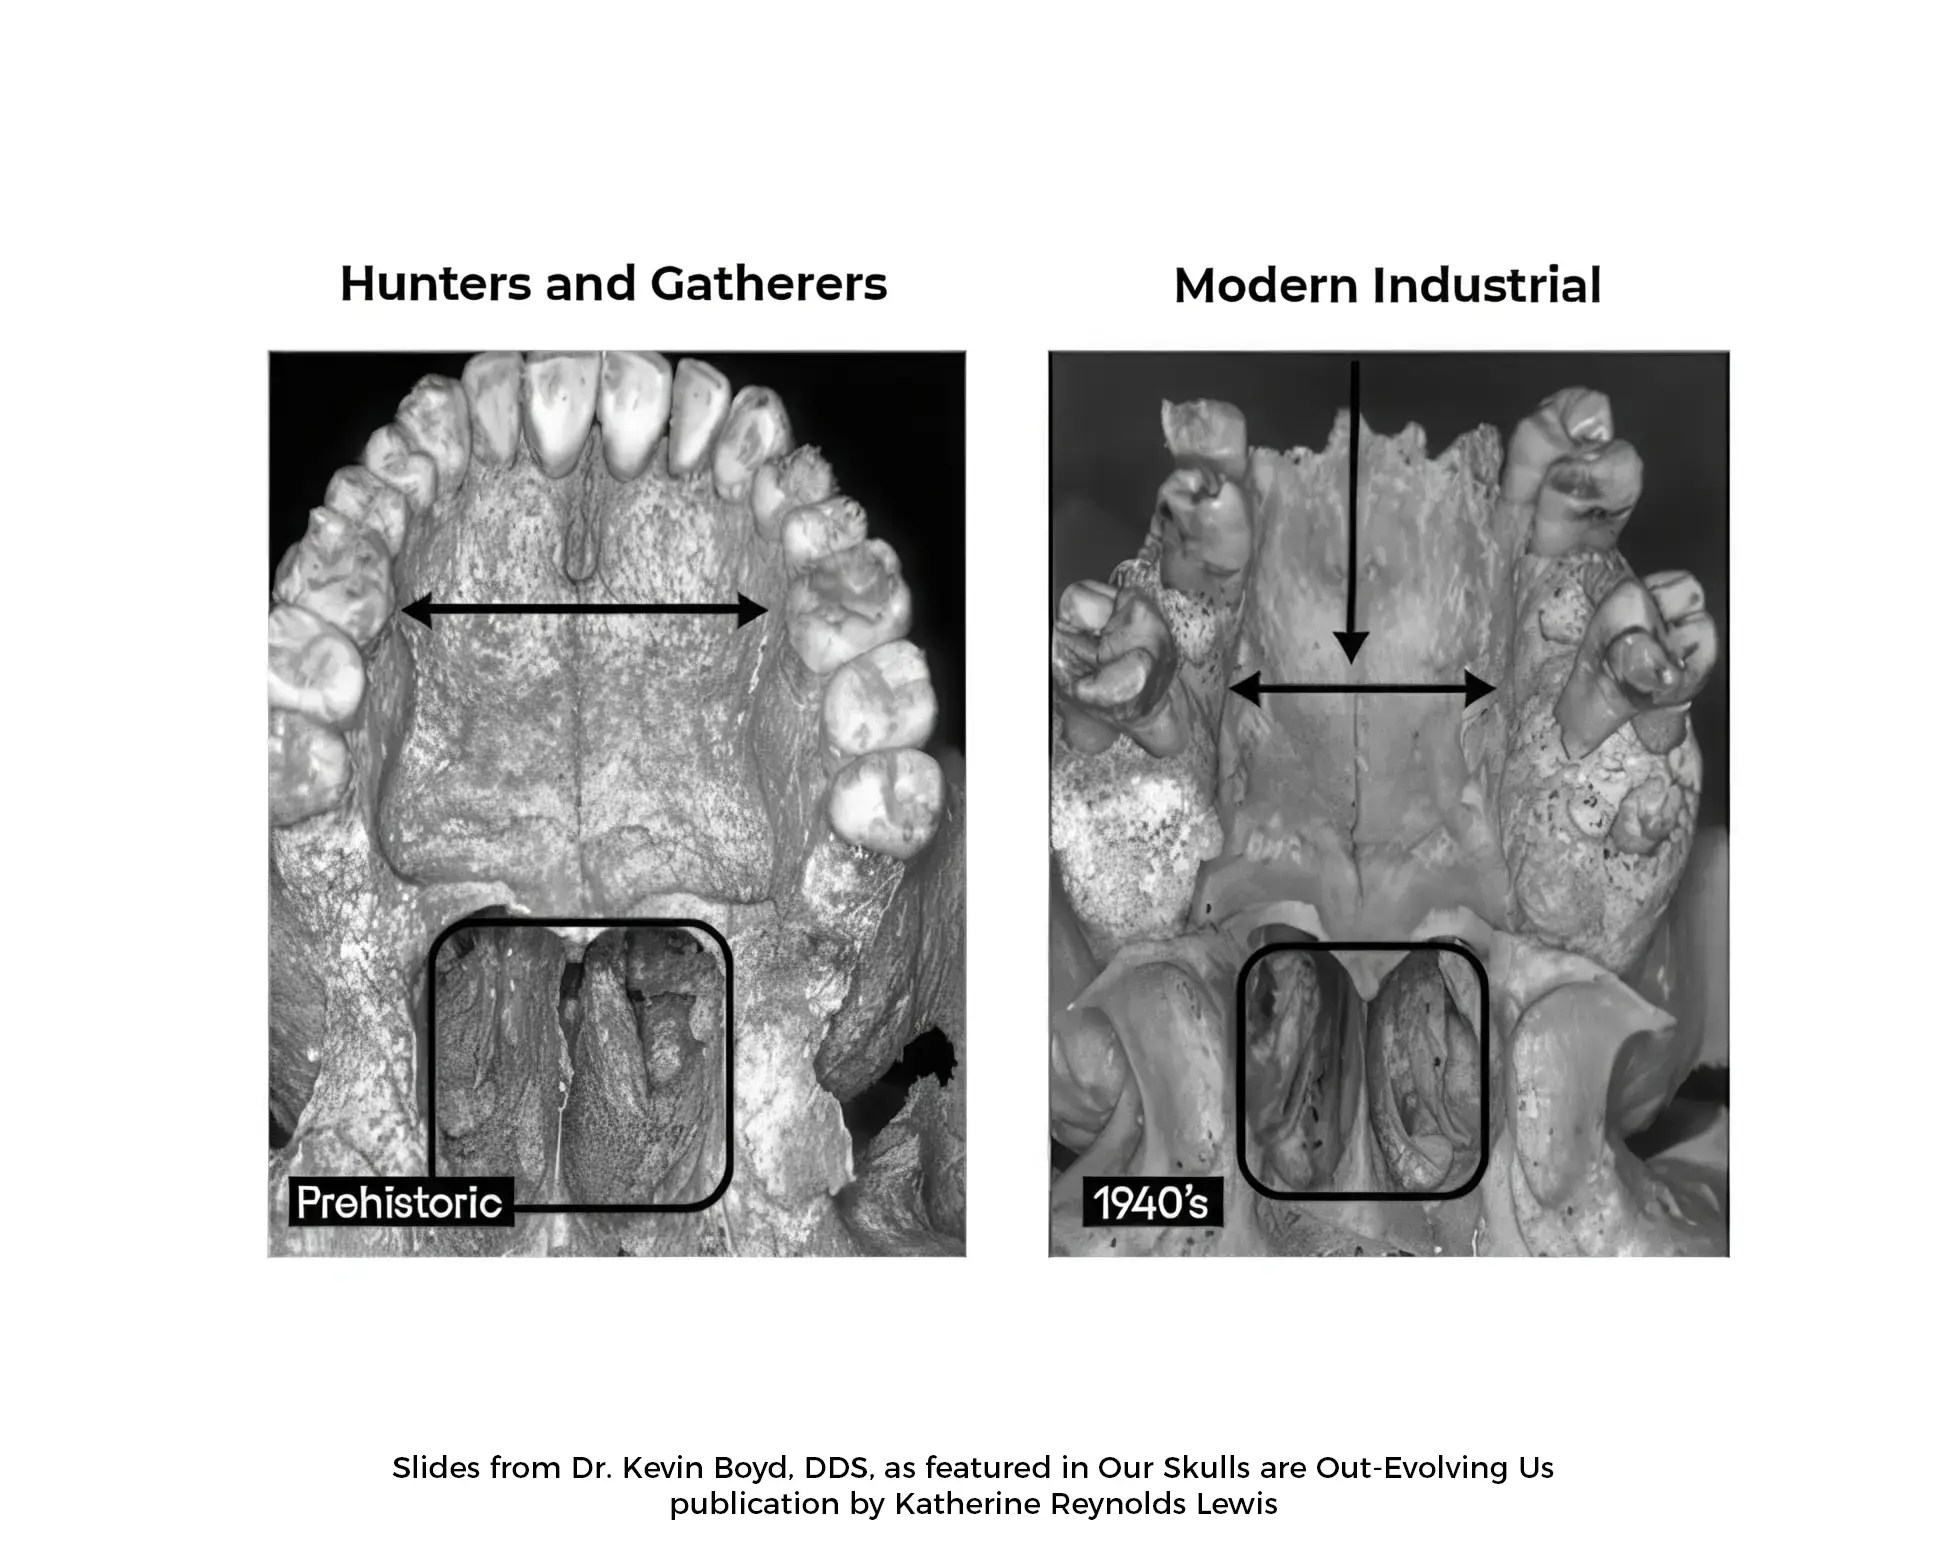

Modern diet and lifestyle has brought with it an epidemic of shrinking human jaws. With this has come altered growth of the lower half of the face surrounding the jaws, collapse of the airway behind the jaws, and compression of the temporomandibular joints (TMJ) associated with the jaws.

Decades of research by brilliant anthropologists, dentists, physicians, and scientists has demonstrated the overwhelming shift in facial development and overall health since the Industrial Revolution, along with the health consequences that have come with it.

- Dr. Kevin Boyd, DDS, Pediatric dentist and researcher on evolutionary jaw changes – Our Skulls are Out-Evolving Us